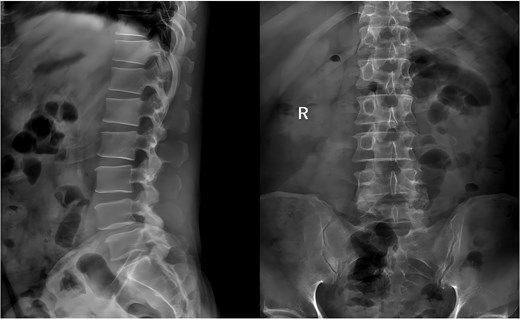

During the surgery, after sufficient decompression at the L4/L5 level and placement of the interbody fusion cage, a complication occurred during the percutaneous pedicle screw insertion. Intraoperative G-arm fluoroscopy confirmed the correct trajectory of the pedicle screw, established by the guidewire and puncture needle, and the pedicle screw was inserted along the established pathway (Fig. 2). However, after removing the guidewire, fluoroscopic imaging revealed that a portion of the guidewire had broken near the anterior margin of the left L5 pedicle screw (Fig. 3). The fracture likely occurred during screw insertion or tightening, which subsequently displaced the broken guidewire toward the anterior vertebral margin. Given the proximity of the fractured guide wire to the anterior vertebral margin, along with the risks of future migration causing injury to adjacent tissues or vessels, as well as the potential for local infection or pain, the decision was made to remove the fractured guidewire after obtaining informed consent from the patient’s legal representative.

Intraoperative fluoroscopic confirmation of guidewire breakage.